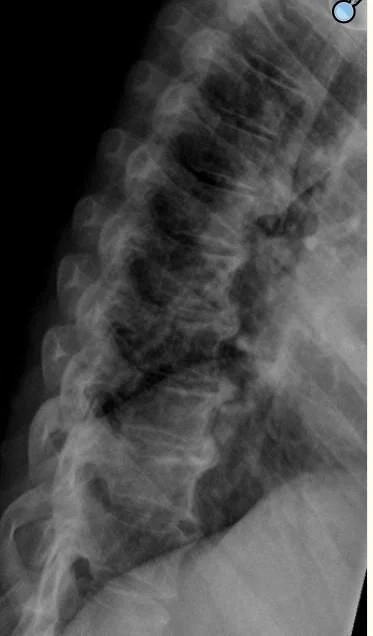

bamboo spine in ankylosing spondylitis

The other condition which may cause osteophytes is diffuse idiopathic skeletal hyperostosis.(DISH). In this condition bone grows into ligaments tendons and joints.  Rather than an autoimmune disease,  it is a radiologic diagnosis with an unknown cause except in the case where the patient is taking isotretinoin. It is   treated with physical therapy and discontinuation of isotretinoin.. It often occurs in males over 50 with diabetes and those taking retinoids. An example is shown below of a patient with DISH who had been treated for acne with isotretinoin. Isotretinoin is a synthetic Vit A derivative that promotes bone growth leading to calcification of ligaments.

35 y.o. with cystic acne treated with isotretinoin and vertebral osteophytes.